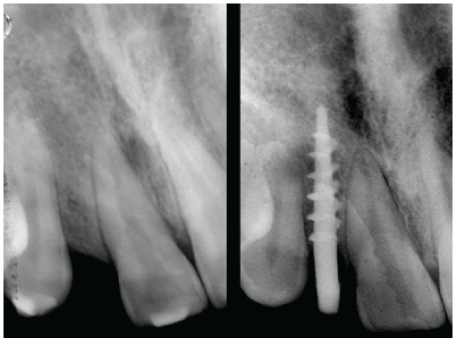

Figure 3: The radiographs: 1 that shows the remaining bone volume. The Pasqualini self-centering burr, which allowed to make an osteotomic tunnel specific for the implant insertion. Two bicortical screws (3.5 mm in the spire) at the end of the procedure.

Figure 7: X-rays show two implants properly set in the bone, which appears to have minimal thickness.